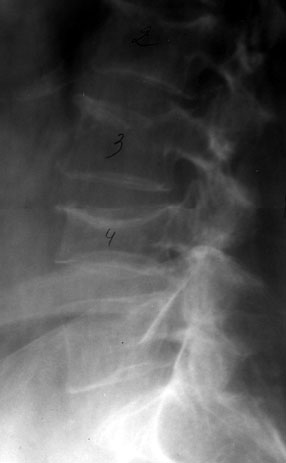

Остеопоротические деформации и переломы позвоночника у больных ревматоидным артритом.

Рис. 2. Двояковогнутая деформация LIV.